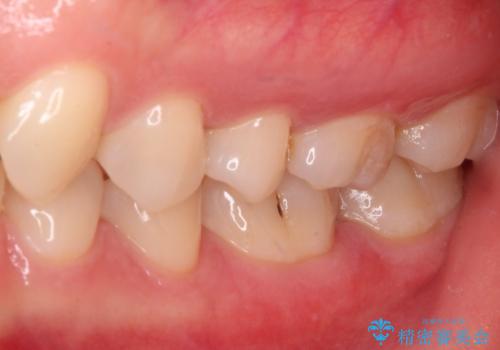

- 奥歯の銀歯と虫歯を気にして来院された患者様です。

下顎は口を開けたときに目立つためセラミックインレーに、上顎奥歯は機能面を優先してゴールドインレーにて修復治療を行うこととしました。

機能面を優先すると、PGAインレー(ゴールドインレー)による修復治療やPGAクラウンによる補綴治療が望ましいのですが、笑ったときに見えている銀歯がどうしても気なってしまうとのことで、目立ってしまう奥歯はセラミックインレーやセラミッククラウンを装着することとしました。

見た目を気にすることなくむし歯治療を行うことができ、患者様に大変満足していただきました。